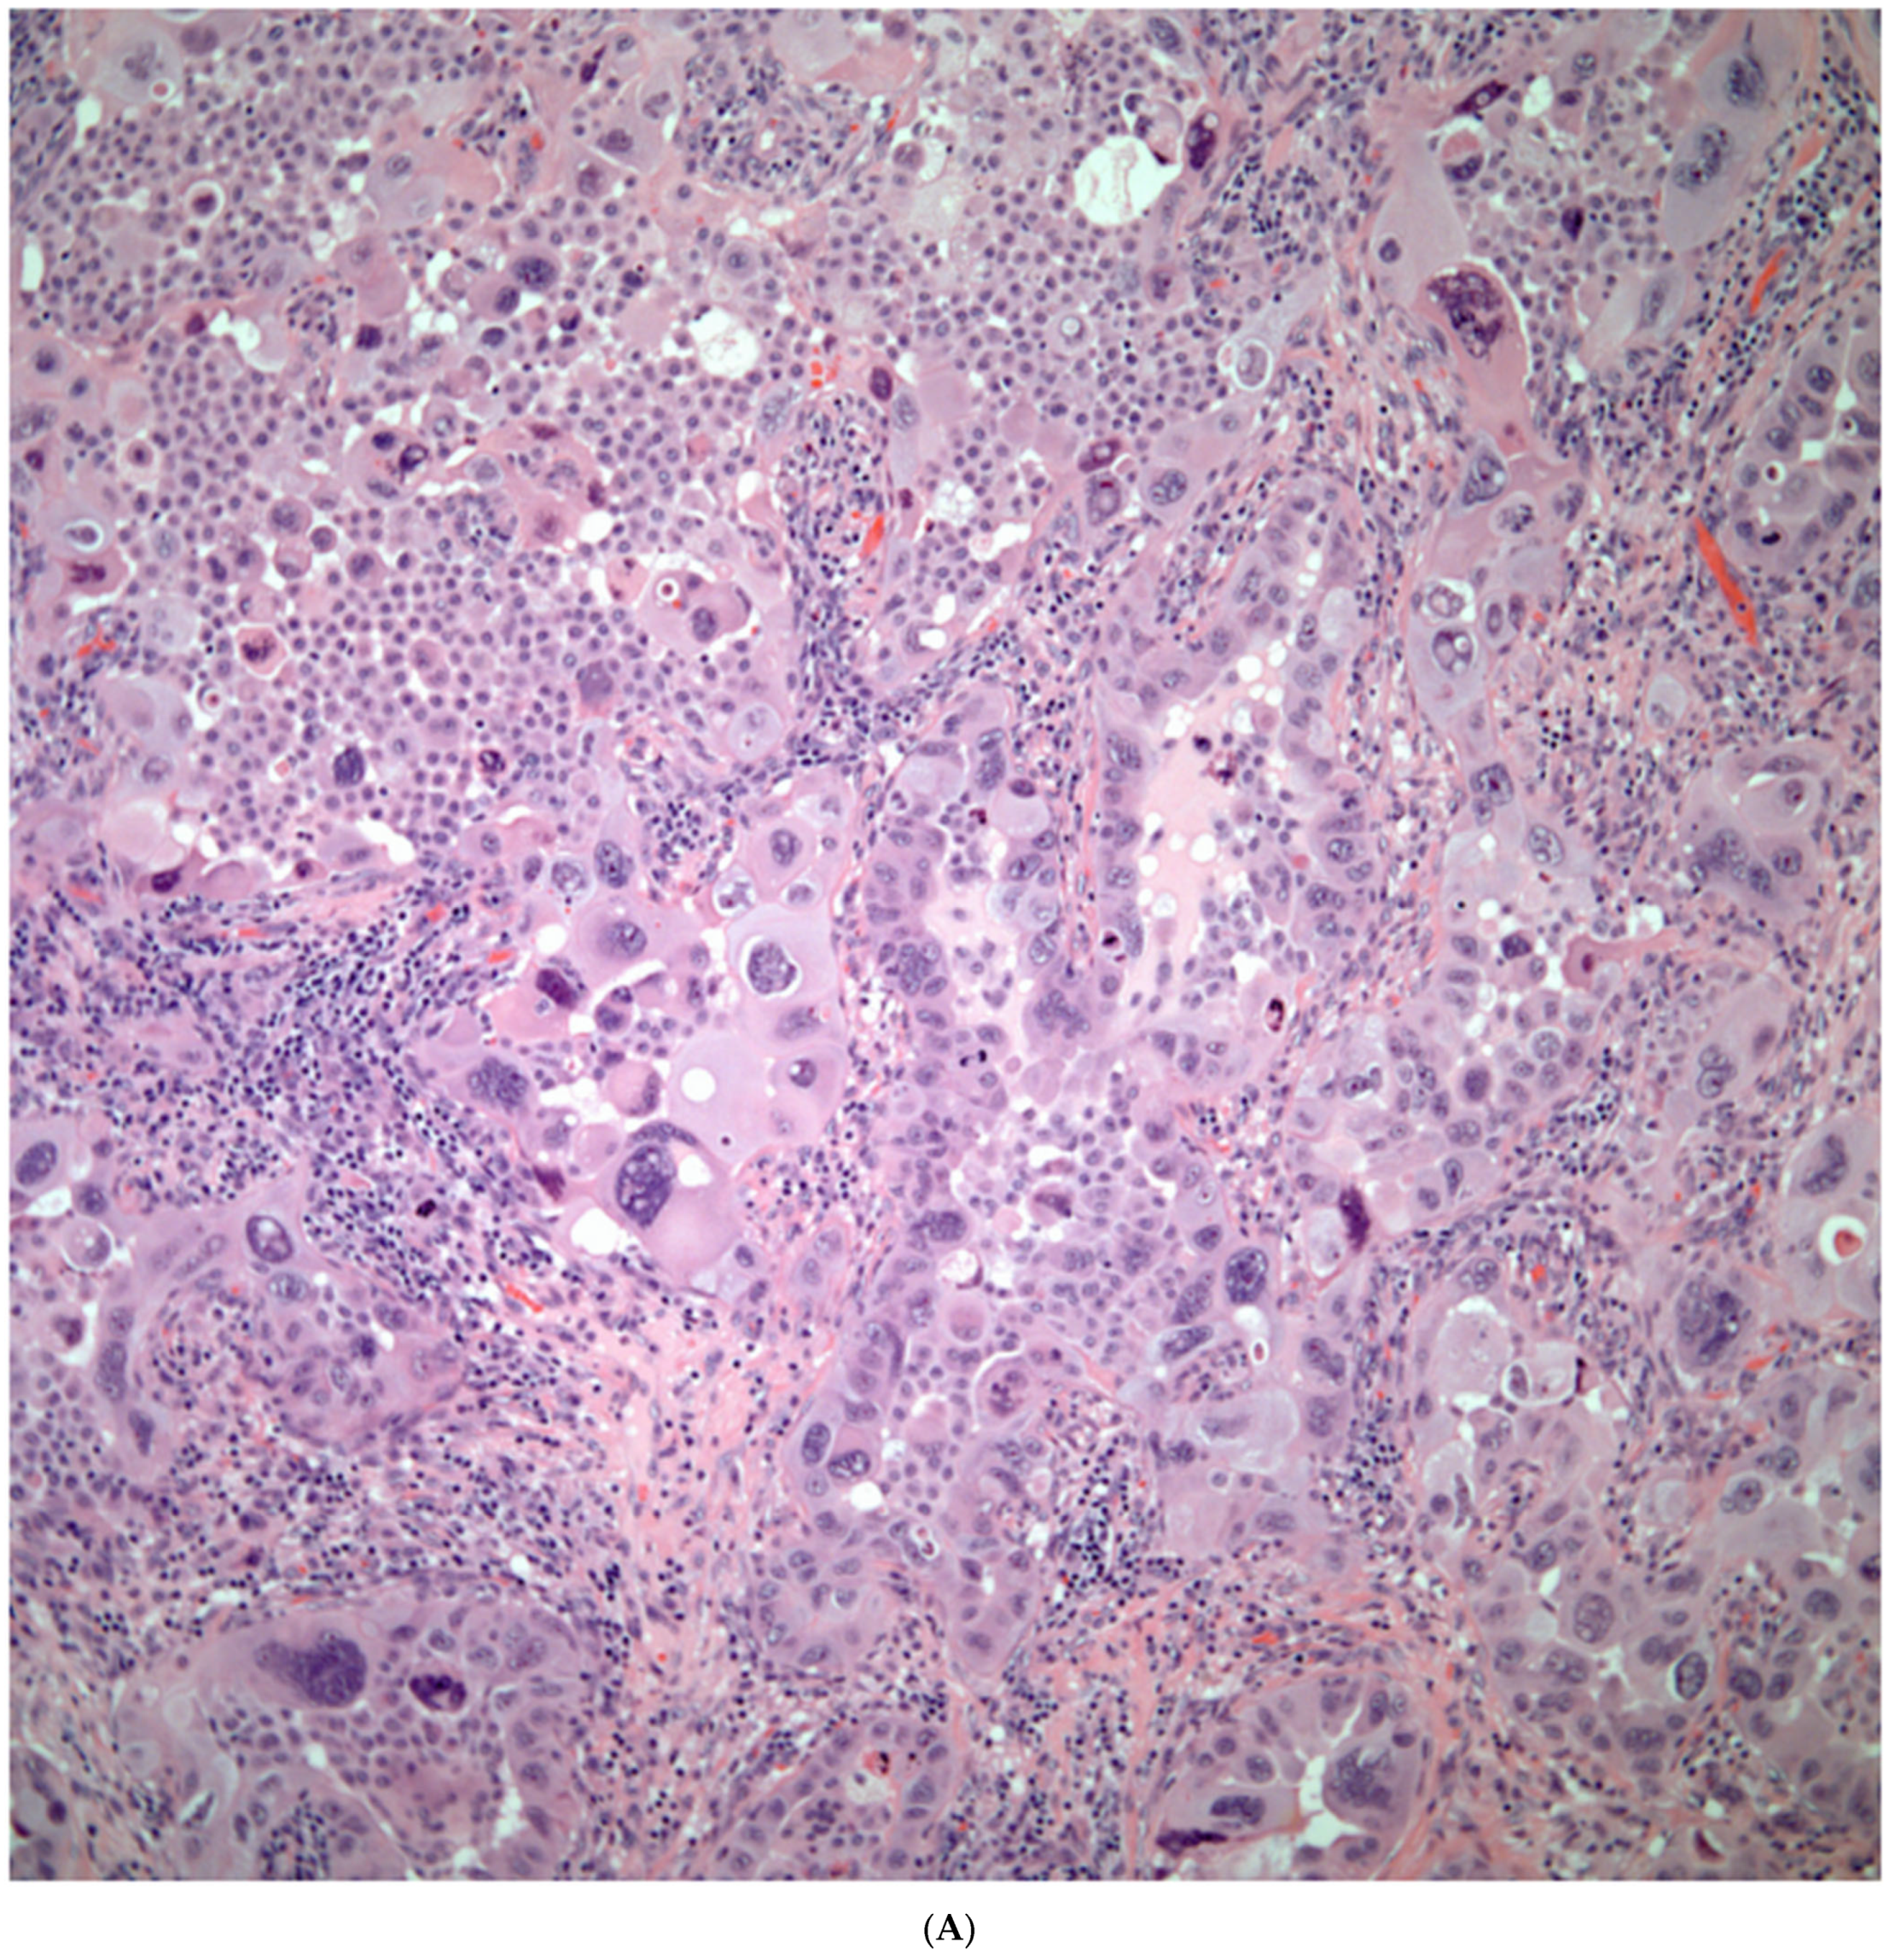

Sarcomatoid carcinomas: These tumors show a tightly packed spindle cell proliferation composed of slender cells with fusiform nuclei and inconspicuous nucleoli, replacing normal lung parenchyma. The tumors are well delimited but not encapsulated (Figure 1). Cellular atypia is variable and may show areas of mild to moderate to marked atypia. Mitotic figures also vary and may be inconspicuous or may be evident with the presence of atypical mitotic figures (Figure 2A,B). In high-grade tumors, the presence of necrosis and hemorrhage is prominent and is mixed with the neoplastic component. Important to recognize is that sarcomatoid carcinomas may be associated with areas of otherwise conventional non-small cell carcinoma such as adenocarcinoma or squamous cell carcinoma (Figure 3A,B). In addition, sarcomatoid carcinoma may also show the presence of bizarre giant cells admixed with the spindle cell component (pleomorphic carcinoma) (Figure 4).

Figure 4.

Sarcomatoid carcinoma with giant cell component (pleomorphic carcinoma).